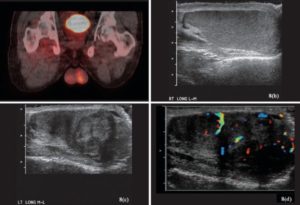

В процессе данного обследования рак яичек диагностируют с помощью изображений, получаемых путем сканирования мошонки звуковыми волнами высокой частоты.

Эта абсолютно безболезненная процедура – один из основных методов, позволяющих врачу определить, является узел злокачественным или доброкачественным. Исследование дает четкое представление о структуре новообразования:

- уплотнения с полостями, заполненными жидким содержимым (кисты), обычно безвредны;

- плотная структура опухоли может быть признаком рака.

Кроме того, во время ультразвукового исследования мошонки специалист определяет положение очага и его размер.

УЗИ

Диагностика болезней мочеполовой сферы подразумевает ультразвуковое обследование мошонки. По характерным эхопризнакам врач определяет:

- локализацию новообразований;

- степень инвазии (прорастания) опухоли в соседние органы;

- наличие патологических изменений во второй железе.

При необходимости назначается УЗИ с допплерографическим исследованием сосудов.